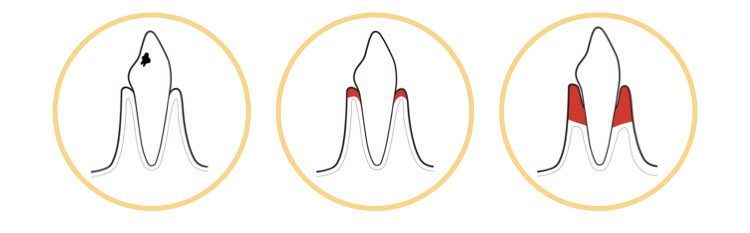

| 1. 龋齿 | 2. 牙龈炎 | 3.牙周病 |

| 4. 修复体周围炎 | 5. 矫正托槽龋齿 | 6. 种植体周围炎 |